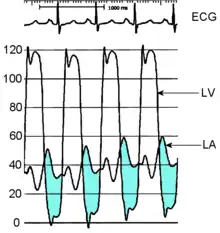

Cardiac chamber catheterization

Another method of measuring the severity of mitral stenosis is the simultaneous left and right heart chamber catheterization. The right heart catheterization (commonly known as Swan-Ganz catheterization) gives the physician the mean pulmonary capillary wedge pressure, which is a reflection of the left atrial pressure. The left heart catheterization, on the other hand, gives the pressure in the left ventricle. By simultaneously taking these pressures, it is possible to determine the gradient between the left atrium and left ventricle during ventricular diastole, which is a marker for the severity of mitral stenosis. This method of evaluating mitral stenosis tends to overestimate the degree of mitral stenosis, however, because of the time lag in the pressure tracings seen on the right-heart catheterization and the slow Y descent seen on the wedge tracings. If a trans-septal puncture is made during right heart catheterization, however, the pressure gradient can accurately quantify the severity of mitral stenosis.